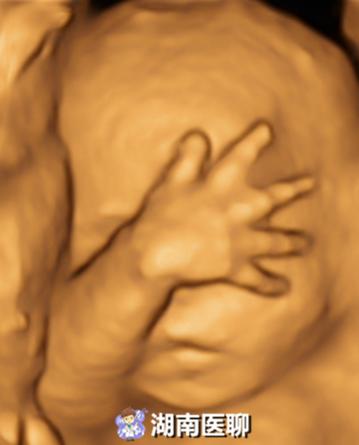

四维:在三维的基础上加入了时间轴,这样就可以显示立体物随着时间推移而变化的动态过程。其实就跟我们平时用手机拍照、录像的道理是一样的,拍照就相当于三维,录像就相当于四维。